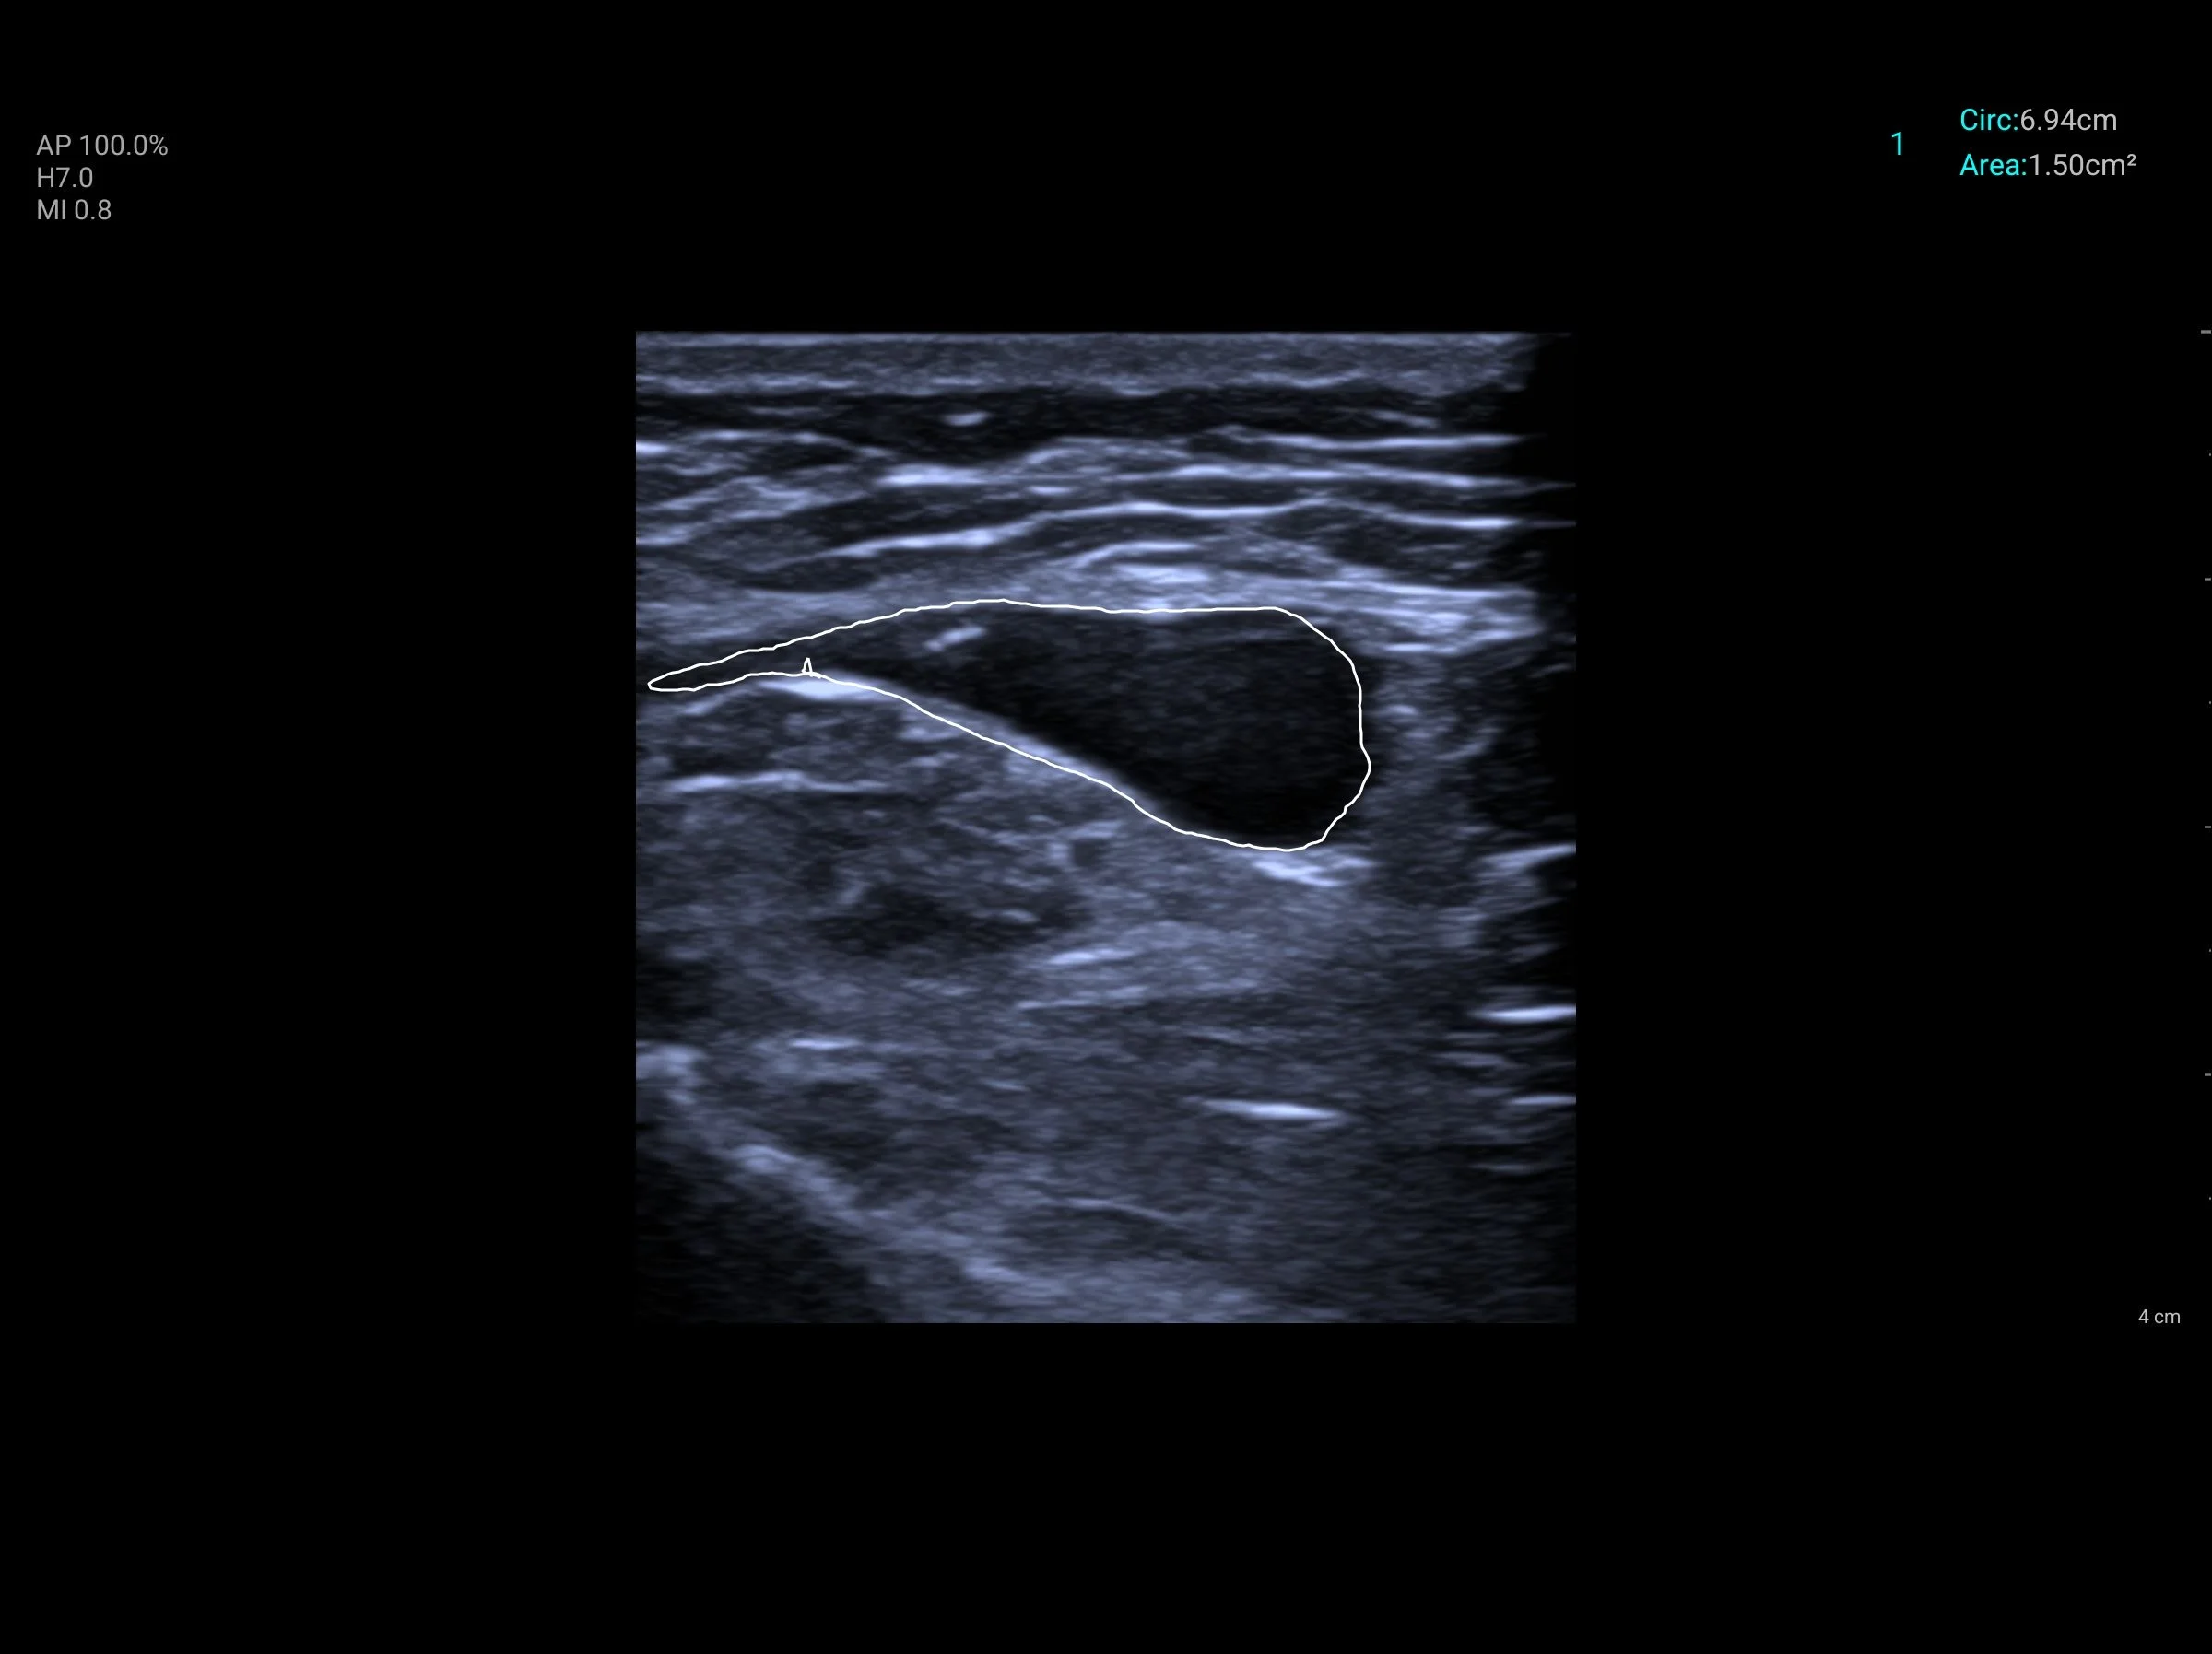

Met behulp van geluidsgolven breng ik uw spieren, pezen, banden, slijmbeurzen en zenuwen in hoge resolutie in beeld op een beeldscherm. Hierdoor zie ik exact wat de interne structuur van uw weefsel is. Zit er een scheurtje in de spier? Is de pees verdikt, ontstoken of zit er een verkalking? Of wordt er een zenuw bekneld door omliggend littekenweefsel?

Ik ben opgeleid volgens de strenge, internationale richtlijnen van SonoSkills. Echografie is voor mij geen eenmalig trucje bij de intake. Ik werk protocol-vrij en gebruik de echo bij vrijwel elke afspraak om de actuele weefselstatus te evalueren. Reageert uw pees goed op de therapie? Neemt de ontsteking af? Door dit continu te meten, stuur ik uw behandeling direct bij waar nodig.

Het echo-onderzoek is volledig pijnloos en onschadelijk. Ik breng een beetje gel aan op uw huid en glijd met de echokop over de pijnlijke regio. U kijkt direct met mij mee op het scherm. Ik leg u in begrijpelijke taal uit wat we zien. Vaak geeft dit alleen al een enorme geruststelling: we weten eindelijk exact wat er aan de hand is.